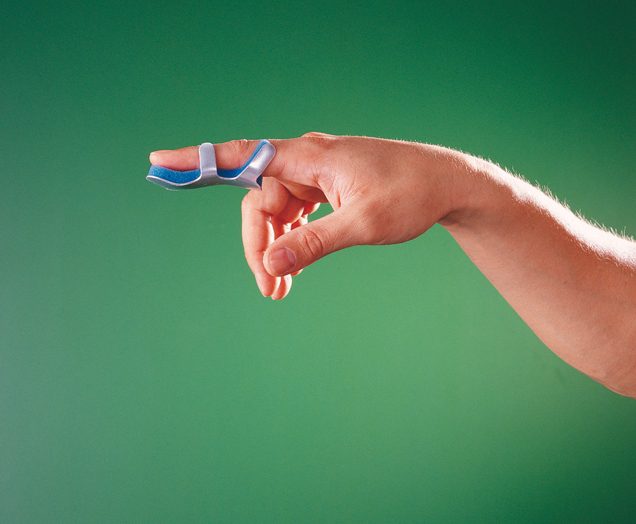

4280 Stabilizatory palców - podwójne mocowanie. Znajdują zastosowanie przy pęknięciach paliczka dalszego oraz urazach stawu międzypaliczkowego dalszego. Miękka wyściółka zapobiega nadmiernemu poceniu się, a ponadto zwiększa komfort przy długotrwałym użytkowaniu stabilizatora. Utrzymują stawy międzypaliczkowe w pozycji wyprostowanej. Numer katalogowy: 4280. Rozmiar: • S; • M; • L

Gwarancja 2 lata

4281 Stabilizatory palców. Zginane końcówki umożliwiają unieruchomienie stawów międzypaliczkowych w wybranej pozycji. Miękka wyściółka zapobiega nadmiernemu poceniu się, a ponadto zwiększa komfort przy długotrwałym użytkowaniu stabilizatora. Zalecane przy pęknięciach paliczka dalszego oraz urazach stawów międzypaliczkowych. Numer katalogowy: 4281. Rozmiar: • S; • M; • L.

Gwarancja 2 lata

4282 Szyna na palec. Służy do podparcia i ochrony podczas złamań z przemieszczeniem. Skierowany ku górze koniuszek szyny ochrania koniec palca. Miękka wyściółka zapewnia wentylację skóry. Numer katalogowy: 4282. Rozmiar: • S; • M; • L.

Gwarancja 2 lata

4283 Stabilizatory obejmujące palec. Znajdują zastosowanie w przypadku urazów koniuszków palców, szczególnie po amputacjach. Służą Również Do unieruchomienia palca w przypadku pęknięć paliczka dalszego oraz urazów stawu międzypaliczkowego dalszego. Miękka wyściółka zapobiega nadmiernemu poceniu się, a ponadto zwiększa komfort przy długotrwałym użytkowaniu stabilizatora. Numer katalogowy: 4283. Rozmiar: • S; • M; • L.

Gwarancja 2 lata

4284 Stabilizatory obejmujące palec. Znajdują zastosowanie w przypadku urazów koniuszków palców, szczególnie po amputacjach. Służą również do unieruchomienia palca w przypadku pęknięć paliczka dalszego oraz urazów stawu międzypaliczkowego dalszego. Miękka wyściółka zapobiega nadmiernemu poceniu się, a ponadto zwiększa komfort przy długotrwałym użytkowaniu stabilizatora. Numer katalogowy: 4284. Rozmiar: • S; • M; • L

Gwarancja 2 lata

4285 Stabilizatory obejmujące palec. Znajdują zastosowanie w przypadku urazów koniuszków palców, szczególnie po amputacjach. Służą Również Do unieruchomienia palca w przypadku pęknięć paliczka dalszego oraz urazów stawu międzypaliczkowego dalszego. Miękka wyściółka zapobiega nadmiernemu poceniu się, a ponadto zwiększa komfort przy długotrwałym użytkowaniu stabilizatora. Perforacja aluminium polepsza wentylację. Numer katalogowy: 4285. Rozmiar: • S; • M; • L.

Gwarancja 2 lata

H-MFS Aparat sztaka.Utrzymują staw międzypaliczkowy dalszy w pozycji wyprostowanej, umożliwiając ruch innych stawów. Aparaty Sztaka oferowane przez nasz sklep medyczny mocuje się do palca za pomocą małego plastra lub bandaża w taki sposób, aby staw międzypaliczkowy dalszy pozostawał w pozycji wyprostowanej. Stosowanie Aparatu Sztaka nie ogranicza ruchu innych stawów.Oferujemy Aparat Sztaka w kilku rozmiarach. Aby dobrać odpowiedni rozmiar aparatu należy zmierzyć obwód stawu międzypaliczkowego dalszego.Numer katalogowy: H-MFS

Gwarancja 2 lata